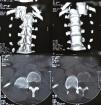

Total vertebrectomy with spine shortening has been reported for the treatment of difficult cases of traumatic spine dislocation, both in acute and chronic phase. We report an exceptional case of a five-week-old T12-L1 spine dislocation in a 25-year-old female with complete paraplegia as a result of trauma in Ciudad de León (Nicaragua). In view of the time since the dislocation, we performed a complete L1 vertebrectomy in order to reduce the dorsolumbar hinge. For osteosynthesis material we had only eight screws and two Steffee plates. We therefore introduced pedicle screws at levels T11, T12, L2 and L3 on the right side and T11, T12, L3 and L4 on the left, and performed manual reduction of the spine. Steffee plates were placed and we added sublaminar wires to reinforce the osteosynthesis. Fifteen months after surgery, there has been no neurological improvement.